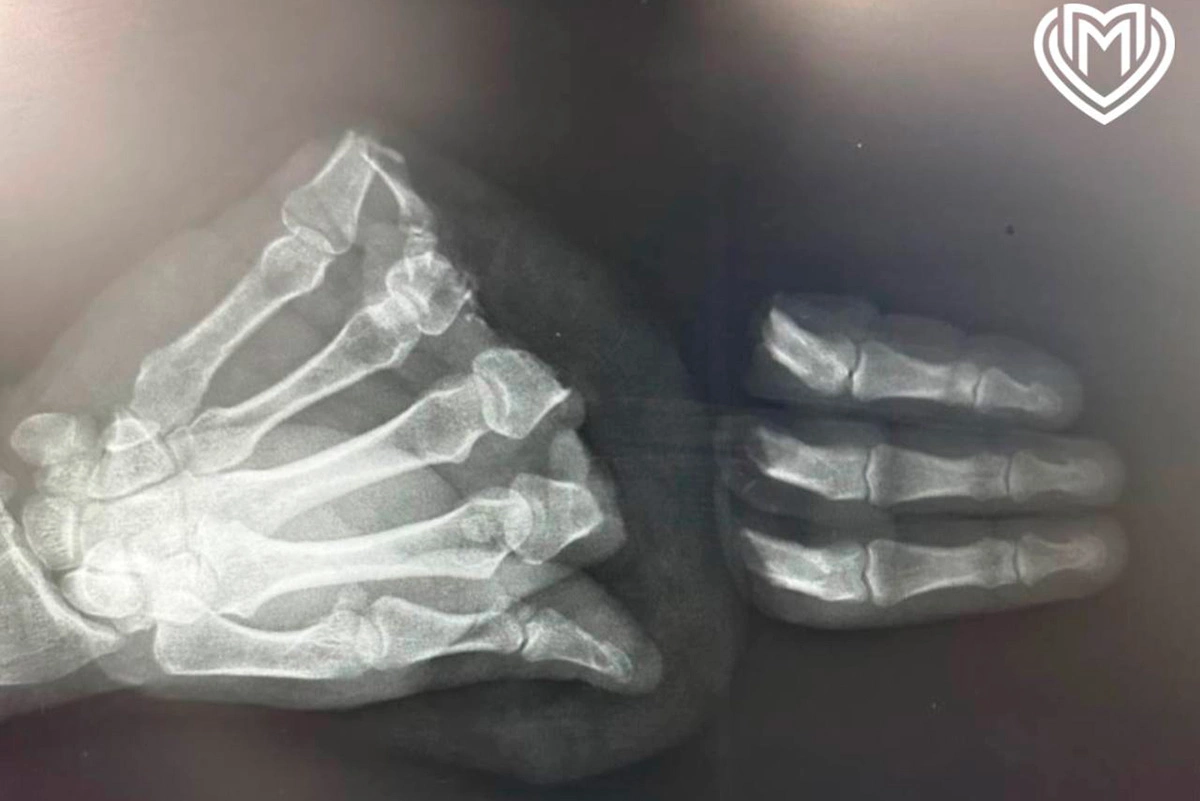

Рентгенгеновский снимок ампутированных пальцев

В Центре микрохирургии кисти в ГКБ имени Ерамишанцева пришили пациенту ампутированные циркулярной пилой пальцы, сообщается в телеграм-канале столичного департамента здравоохранения. Мужчина повредил правую руку во время домашних работ.

«Из-за механизма травматического отчленения и повреждения мягких тканей ампутированных сегментов операция проходила с техническими трудностями и длилась почти 13 часов: три ампутированных пальца были реплантированы полностью, а пятый палец (мизинец) ввиду дополнительных повреждений мягких тканей восстановить не представлялось возможным», — уточнили в больнице.